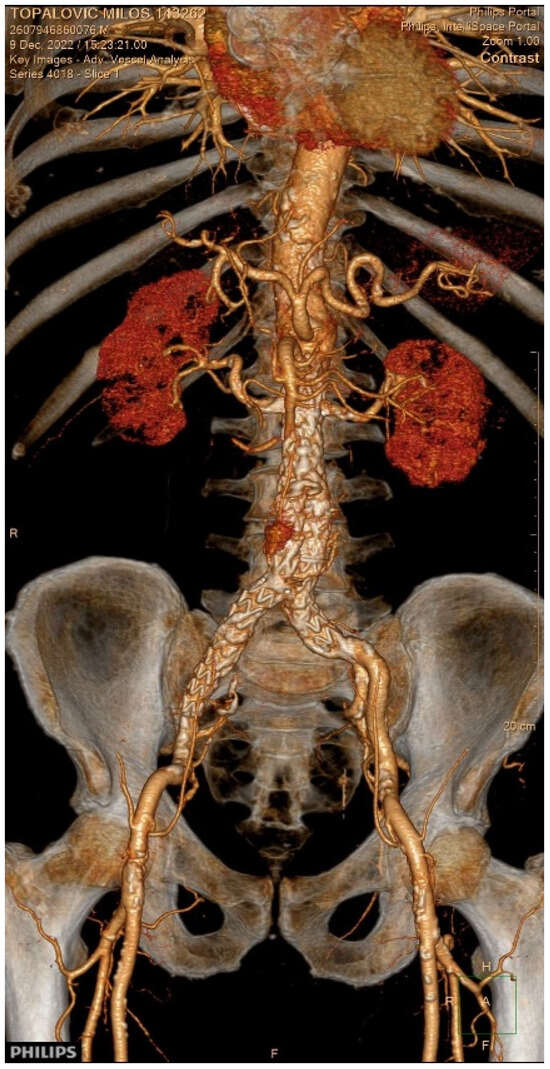

Show Figures

Figure 1